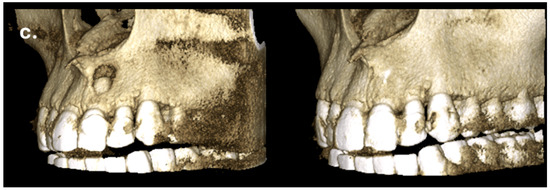

The patient returned for a follow-up visit two years later. The tooth was asymptomatic, and the radiograph showed no signs of periapical radiolucency (Figure 5a). The caries lesion on the mesial surface was treated. Eight months later, a new CBCT scan was performed by another dentist due to a traumatic injury on the right side of the jaw. Upon reviewing the scan, valuable diagnostic information became apparent, including complete restoration of the cortical bone, reestablishment of healthy periapical tissues, and the absence of any radiolucency around the apex of tooth #21. The CBCT PAI score was recorded as 0, indicating complete healing (Figure 5b,c).

Figure 5.

Complete regeneration of the apical bone fenestration observed over a period of two years and eight months: (a) periapical radiograph showing resolution of the periapical radiolucency; (b) CBCT scan confirming re-establishment of the cortical bone and healthy periapical tissues; (c) the 3D reconstruction is included to illustrate the anatomical changes before and after treatment.

Successful treatment at the two-year follow-up was confirmed through clinical examination, absence of patient complaints, and a periapical radiograph. Despite the diagnostic advantages of CBCT, it is not recommended as a routine imaging method for follow-up, even in limited field-of-view settings, in order to minimize patient radiation exposure [14,30]. However, eight months later, the patient experienced a traumatic injury to the right frontal facial region, and a CBCT scan was performed by another clinician. Under these circumstances, it became possible to observe and confirm three-dimensional healing of the lesion, as well as reconstruction of the buccal cortical bone plate, indicating closure of the fenestration. These findings, also visible on the periapical radiograph, support the effectiveness of the non-surgical endodontic treatment approach in cases of bone fenestration.